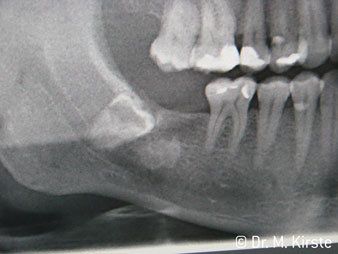

Die professionelle Lagergestaltung im Innenleben des Handstückkopfes garantiert einen ruhigen Lauf der Bohrer, bei der Zahn- oder Wurzelseparation (Abb. 4 - 9) zeigt sich ein beeindruckendes Schnittbild ohne Schlageffekte.